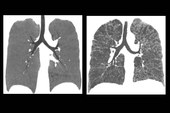

Primeiro: abandonar o cigarro. Além disso, entre os 50 e 80 anos, os pacientes de alto risco devem se submeter, uma vez por ano, a uma tomografia de tórax de baixa dose de radiação. Capaz de detectar tumores em fase inicial, quando as chances de cura são de 90%, essa rotina, segundo estudos recentes, reduz em 20% as taxas de mortalidade. Pacientes de alto risco são aqueles que fumam 20 maços ou mais por ano ou mais e ex-fumantes que largaram o vício há menos de 15 anos.

Imagem: Isabela Silva Müller/Divulgação